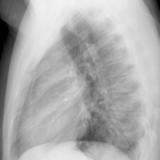

Case 8b Thymoma Lat

Date: 03/27/2009

Views: 14171